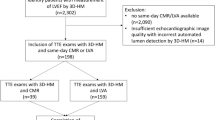

The institutional review board approved the study and all patients gave written informed consent. From June 2008 to August 2008, all patients referred to our centre with a clinical indication of cardiac MRI were invited to participate in the study. Exclusion criteria were as follows: age <18 years; contraindication for MRI; arrhythmias during cardiac MRI examination; CHD; and patients referred for an examination that did not include ventricular function analysis (i.e. MR angiography of pulmonary veins or thoracic aorta). The target sample size (60 patients) was defined from the results of a literature study. Baseline population characteristics are summarised in Table 1. Sixty consecutive patients were included. Mean patients’ age was 53.5 ± 17.5 years and 42 (70%) were male. Clinical indications were represented by a panel of the currently most frequent cardiac MRI indications in patients with AHD.

Semi-quantitative RV parameters (TAPSE, RVFS and RVFAC) were determined using a 4-chamber view cine sequence (Fig. 1). TAPSE is the difference between ED and ES RV length. These lengths are measured from the lateral part of the tricuspid annulus to the RV apex. RVFS is the TAPSE indexed to the ED RV length. To determine RVFAC, ED and ES RV areas were measured on a 4-chamber view; RVFAC was obtained by dividing the difference between the ED and ES areas by the ED area. As for Qt measurements, trabeculae and papillary muscles were included in the RV cavity for RVFAC measurement. For all SQt measurements, RV ED and ES were defined respectively as images with the largest and the smallest RV cavity area. To evaluate intra- and inter-observer variability and the effect of previous experience, each SQt analysis was performed twice at least 1 month apart.